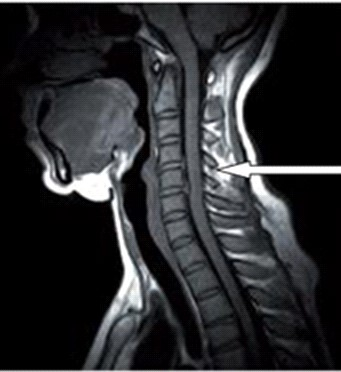

Na obrazie rezonansu magnetycznego strzałką oznaczono wyrostek kolczysty kręgu

Ilustracja do pytania 27

A. szyjnego w płaszczyźnie strzałkowej.

B. szyjnego w płaszczyźnie czołowej.

C. piersiowego w płaszczyźnie czołowej.

D. piersiowego w płaszczyźnie strzałkowej.